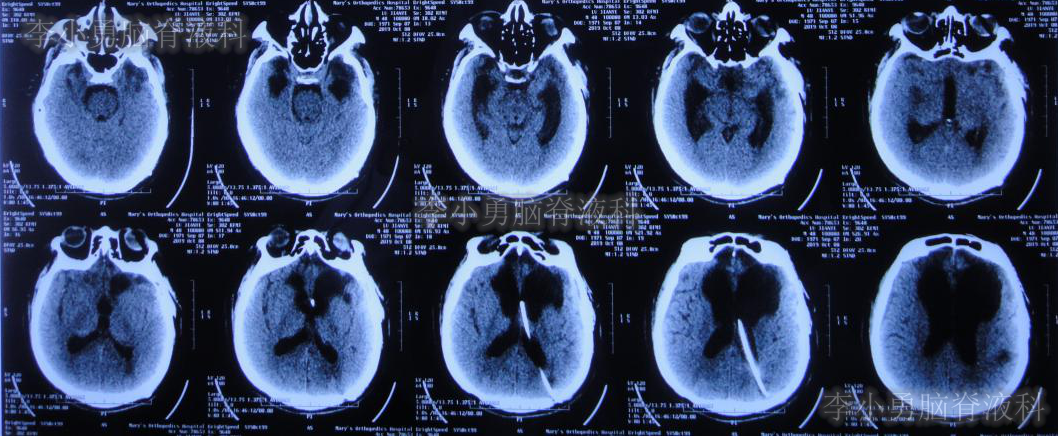

2019年3月12日即开颅术后71天,从山西太原转至北京某三甲医院;住院时复查头颅CT(图-2)示双侧侧脑室扩张,右侧硬膜下积液并少量出血,减压窗处脑膜脑膨出。

图-2:2019年3月12日头颅CT

入院1周后即2019年03月19日即开颅术后78天,进行了左侧额部颅骨缺损钛板修补术+脑室腹腔分流术。术后当天复查头颅CT(图-3)示右侧脑室内可见分流管,左侧颅骨修补术后改变,但右侧仍有硬膜下积液合并出血。

图-3:2019年3月19日头颅CT

在山西三甲医院治疗13天后,于2019年4月9日即颅骨修补术+脑室-腹腔分流术后21天,再次转回北京某三甲医院。入院当天复查头颅CT(图-5)示脑室引流术后状态。

图-5:2019年4月9日头颅CT

2019年4月22日即脑室-腹腔分流术后34天,第3家医院住院第2天再次出现发热38.6℃,并行头颅CT(图-6)检查示仍为脑室引流术后状态;但胸部CT(图-7)检查示肺炎。

图-6:2019年4月23日头颅CT

虽然已显示出脑积水加重的表现,但医生仍考虑发热为肺部感染引起,因此给予抗菌素治疗2月余。但发热仍难以控制,并且患者意识也逐渐恶化至昏迷的状态,肢体活动亦明显减少。2019年7月2日(颅骨修补术+脑室-腹腔分流术后105天)复查头颅CT(图-8)示脑室进一步扩大。无奈此时再次给予腰椎穿刺,但脑脊液化验仍不支持“颅内感染”。

图-8:2019年7月2日头颅CT

颅骨修补术+脑室腹腔分流术后105天即2019年7月12日(脑外伤术后194天),转至李小勇脑脊液科。入院时:患者呈昏迷状态,体温高,留置胃管、气管切开套管(图-9)。入院当天行头颅CT(图-10)示脑室扩张、腹部CT检查(图-11)可见肝区巨大的囊肿,其内可见引流管,考虑囊肿内为脑脊液。

图-10:2019年7月12日入院时头颅CT

由于患者脑室明显扩大,且肝区巨大水囊(引流管包裹形成),考虑分流管已发生堵塞,故入院当天紧急行脑室外引流术+原分流管拔除术。术后次日复查头颅CT(图-12)示引流管位置良好,无出血。

图-12:2019年7月13日头颅CT

术中留取的脑脊液标本培养5天后回报为表皮葡萄球菌,给予抗感染治疗。经过20天的治疗,患者脑脊液中细菌消失,且发热症状消失。于2019年8月6日常规复查头颅CT(图-15)示脑室略缩小,当日改行脑室长程引流术。

图-15:2019年8月6日头颅CT术前复查

术后常规复查头颅CT(图-16)示引流管位置良好。

图-16:2019年8月6日头颅CT术后复查

分流术后10天,即2019年10月9日,饮食变正常,神志完全清楚(图-18),常规给予复查头颅CT(图-19)示脑室进一步缩小。

图-19:2019年10月9日头颅CT脑室进一步缩小